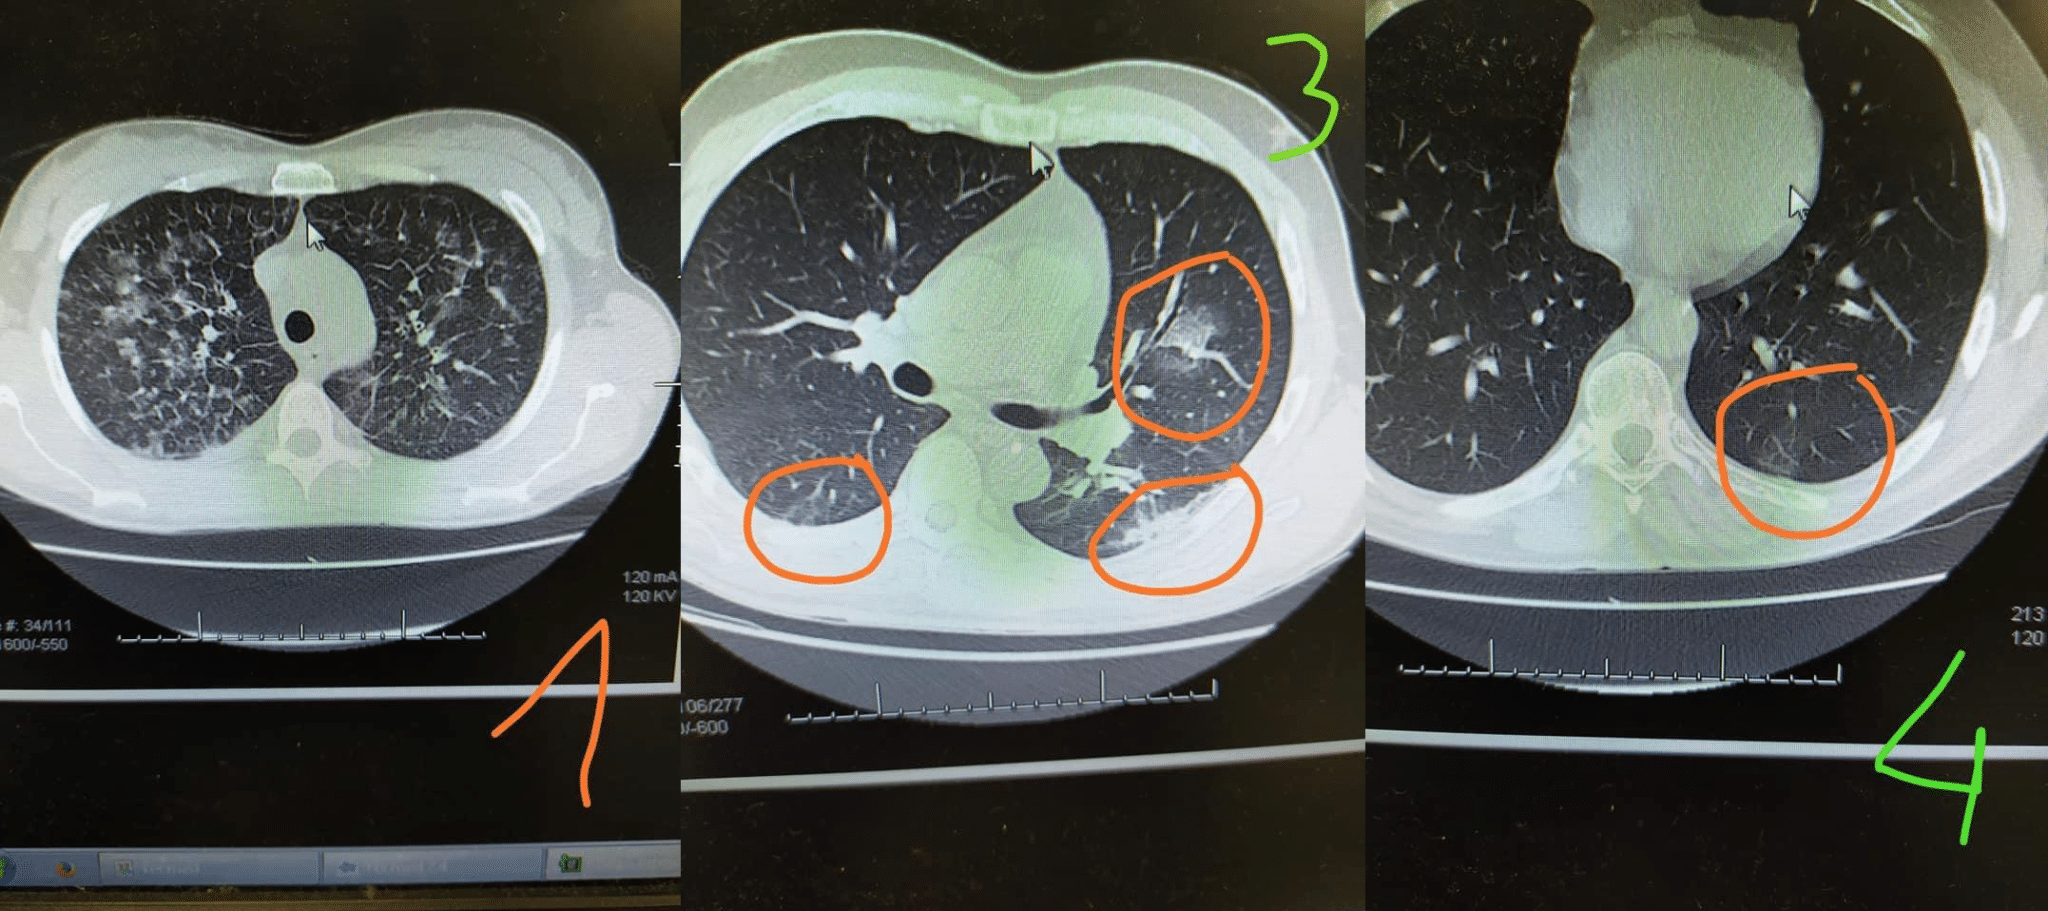

Attilio Galmozzi, medico dell’ospedale di Crema, ha pubblicato su Facebook le immagini TAC dei polmoni di pazienti Covid tra marzo e settembre. “Pubblico queste immagini per cercare di veicolare un messaggio semplice e di speranza. Le immagini si riferiscono a TAC di pazienti Covid collocate tra marzo e settembre. Dico subito, a scanso d’equivoci, che le immagini 3 e 4 di settembre sono di pazienti giovani, una con una insufficienza respiratoria, l’altro asintomatico. Niente terapia intensiva”, ha specificato il medico. “E questo ad oggi è un dato buono, perché i sacrifici fatti dalla popolazione hanno certamente ridotto il carico di malattia”.

Galmozzi ha spiegato cosa vediamo nelle immagini pubblicate via social: “Nell’immagine 1 è facilmente intuibile come la polmonite interstiziale sia bilaterale (maggiore a destra) e che il quadro fosse molto severo. Nella 3 e nella 4 il carico di malattia (i segni “a vetro smerigliato”) sono limitati e i quadri clinici meno impegnativi. I pazienti le cui TAC sono la 3 e la 4 sono recenti e fanno parte di quel piccolo numero di positivi (come diciamo sempre, il virus circola ancora anche se da meno malattia, ma la può dare ancora). La 1 è di marzo, piena emergenza globale quando si vedevano 70-80 polmoniti al giorno”.